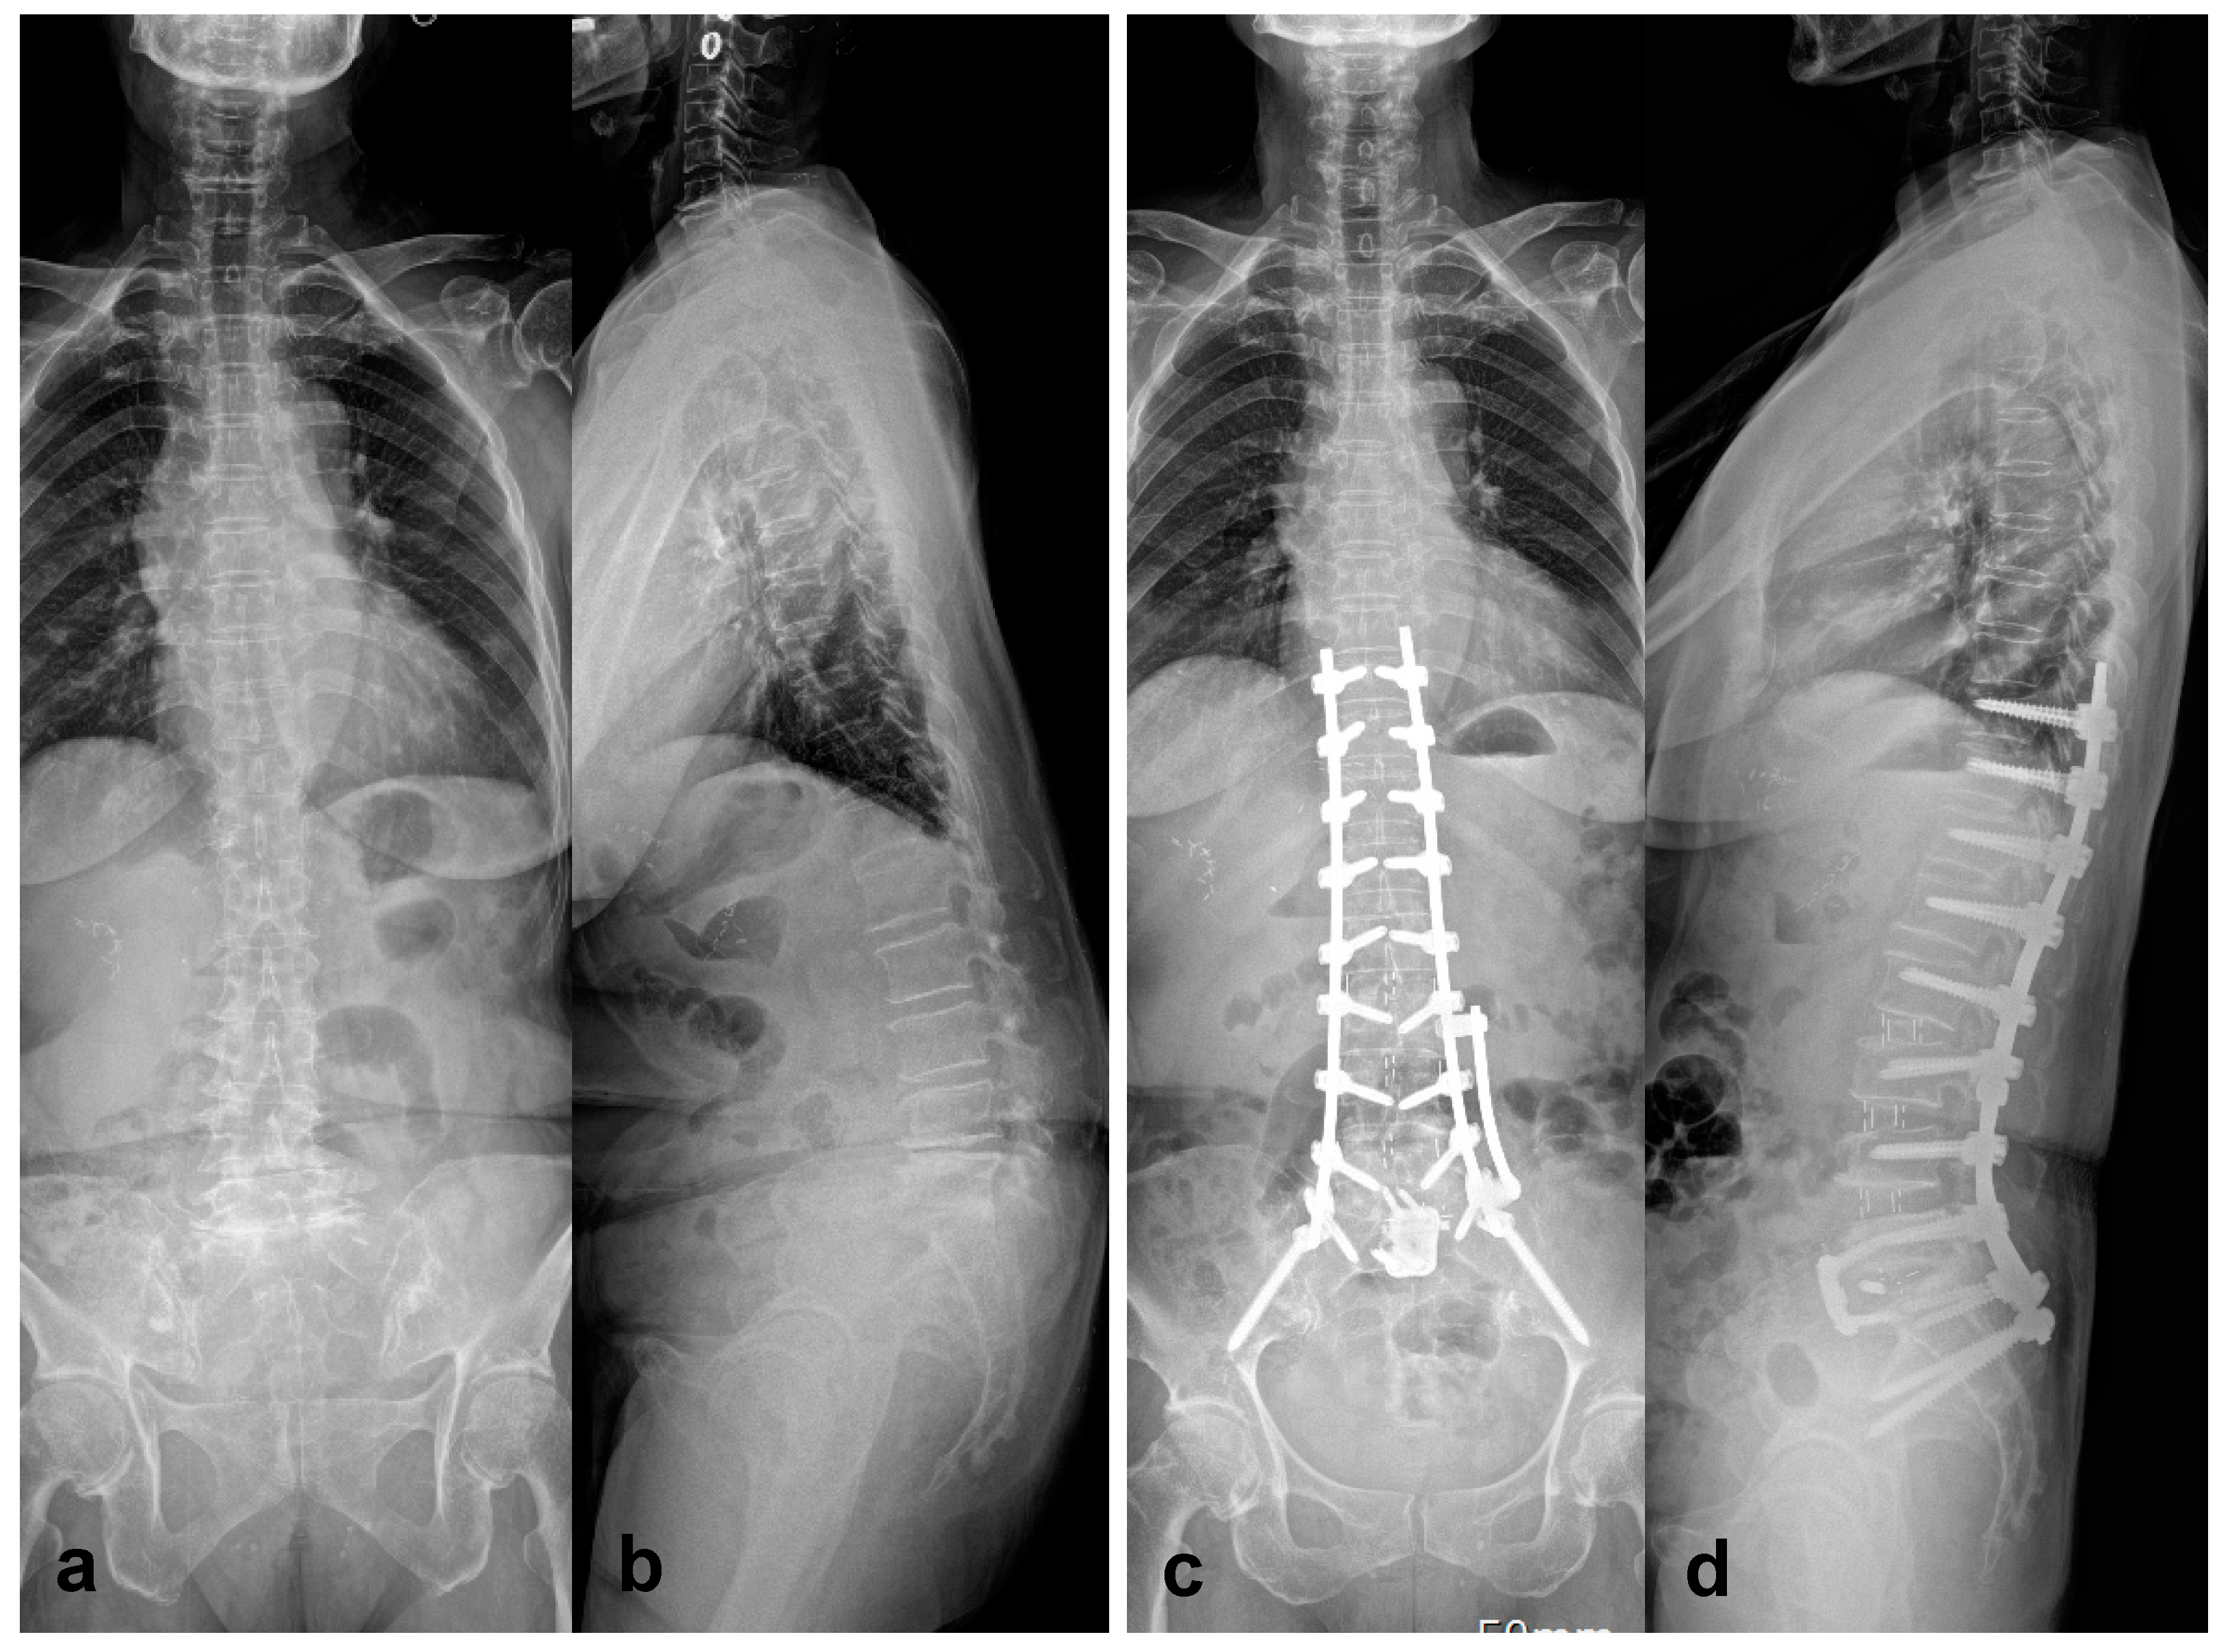

- Park, S.W.; Ko, M.J.; Kim, Y.B.; Le Huec, J.C. Correction of marked sagittal deformity with circumferential minimally invasive surgery using oblique lateral interbody fusion in adult spinal deformity. J Orthop Surg Res 2020, 15, 13–21. [Google Scholar] [CrossRef] [PubMed]